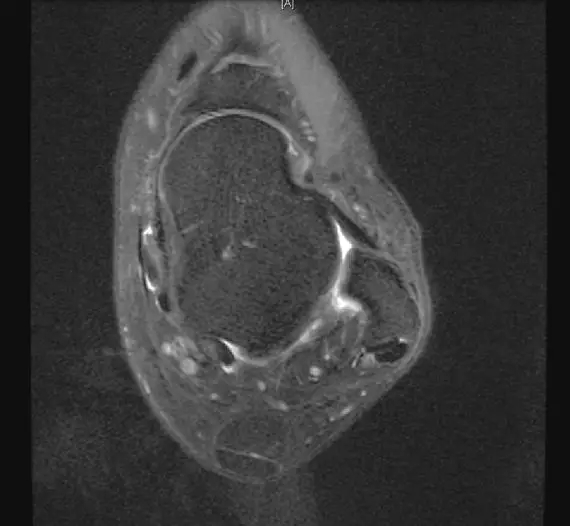

从这张片子我们可以看到正常的韧带结构,包括距腓前韧带,跟绯韧带,它是质地比较均一,T2相高信号,连续性良好,并且有良好的张力,从冠状位也可以看到跟绯韧带,在腓骨肌腱的深方,也是T2相跟T1相的低信号,有良好的连续性,张力也不错。